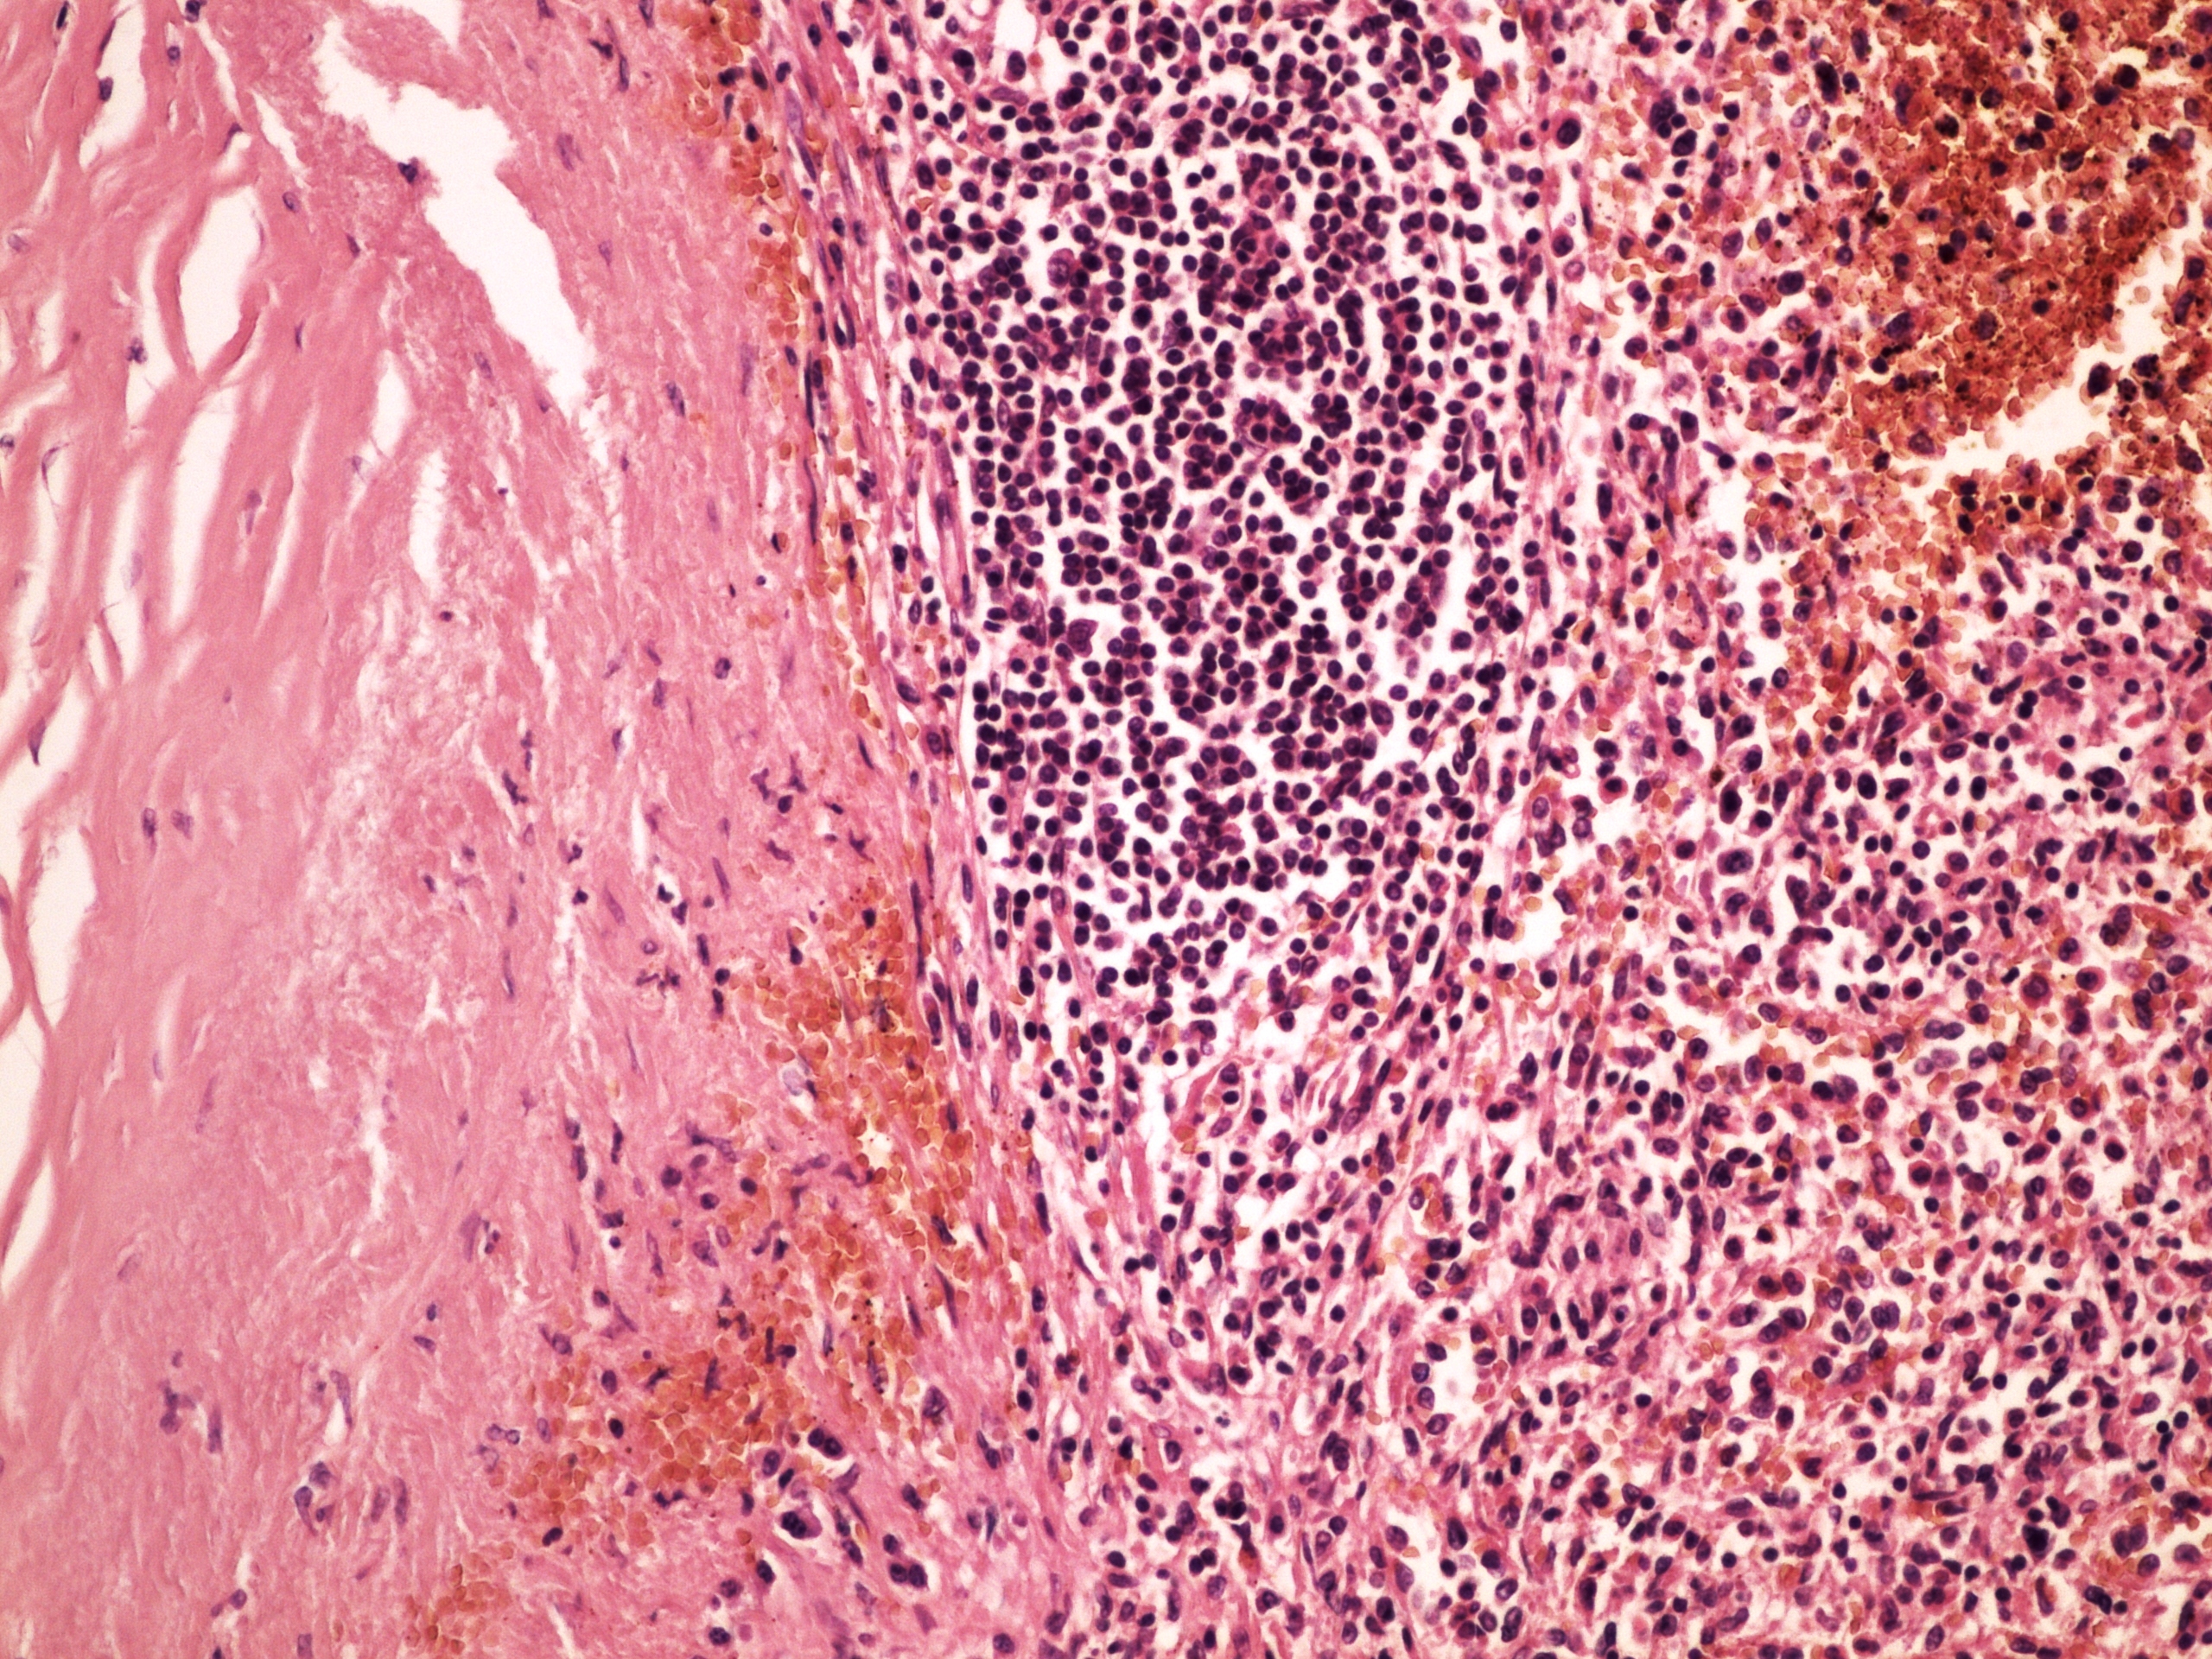

Preparát č.17 a č.18 - perisplenitis cartilaginea

Struktury

- ložiska vaziva